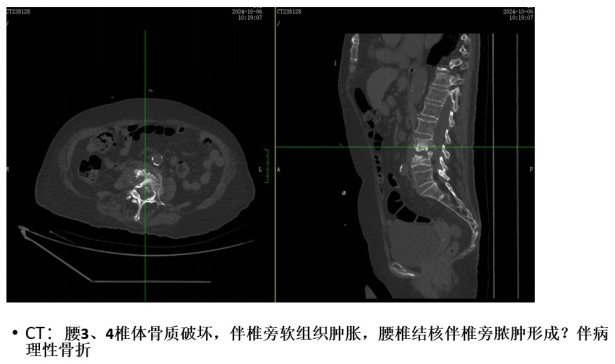

為解決老人病痛,脊柱外科錢軍博士團隊對其進行了詳細的查體以及全面細致的評估,診斷為L3、4脊柱結(jié)核伴病理性骨折、椎旁膿腫,患者腰部疼痛癥狀逐漸加重,病灶已經(jīng)壓迫神經(jīng)引起了截癱。